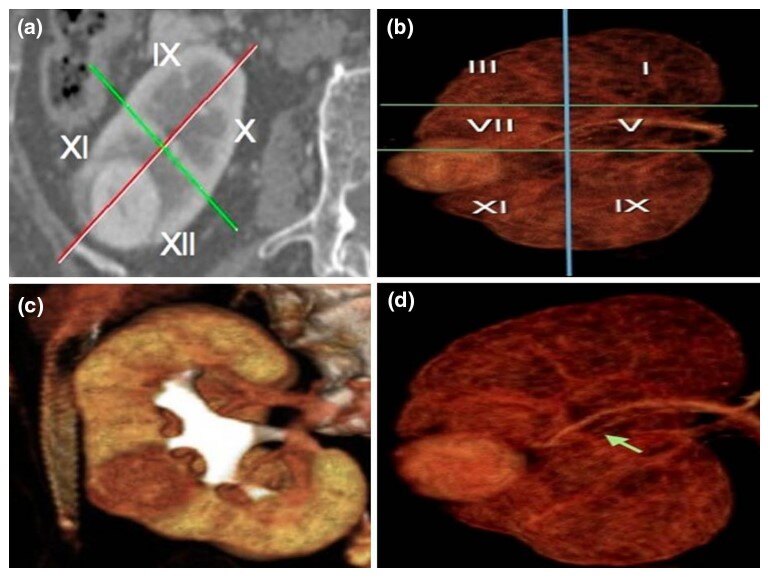

新型影像学和计算机辅助三维重建下的解剖结构细化:可以更好的减少缺血时间,尽早开放阻断的血管,间歇性阻断血管,超选阻断和无阻断血管。

新型节段性肾脏解剖: 精准描述肿瘤分割部位,大小和血供;计算机辅助PVA模型: 依据术前影像计算剩余实质体积,评估术后发生慢性肾功能不全的概率